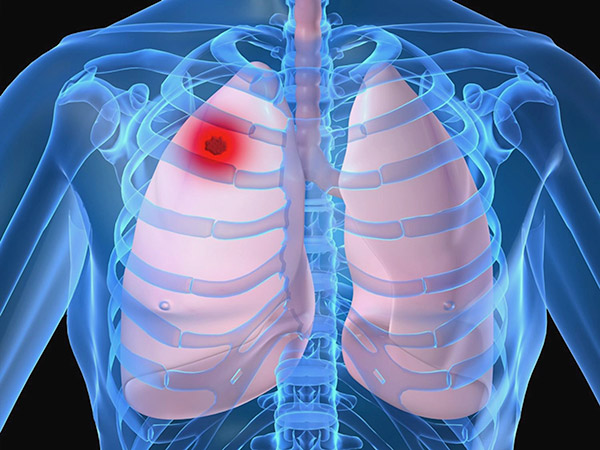

Saiba maisCâncer de Pulmão

O câncer de pulmão é mais frequente em pessoas com mais de 65 anos de idade, especialmente aquelas que fumaram durante a vida. Como a doença não causa sintomas evidentes na fase inicial, é comum que o diagnóstico ocorra quando a doença já se encontra em estágio avançado.